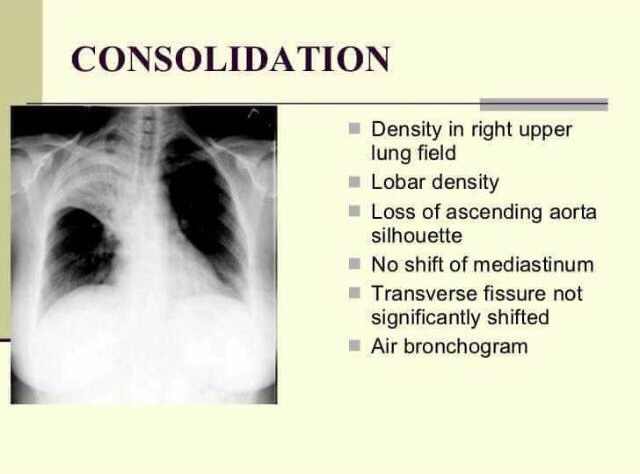

5) LUNG ABSCESS & CONSOLIDATION

➡️ Airspace opacification

- filling of the alveoli with infectious material and pus

- initially patchy

- becomes confluent as infection develops

➡️ Air bronchograms